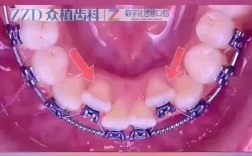

咬合干扰与早接触

- 表现:正中咬合时某颗牙齿先接触,导致下颌偏向一侧,或咀嚼时某颗牙齿酸痛、敏感。

- 原因:矫正后期牙齿移动后,未充分调磨高点;或保持器佩戴不当,牙齿轻微移位导致咬合变化。